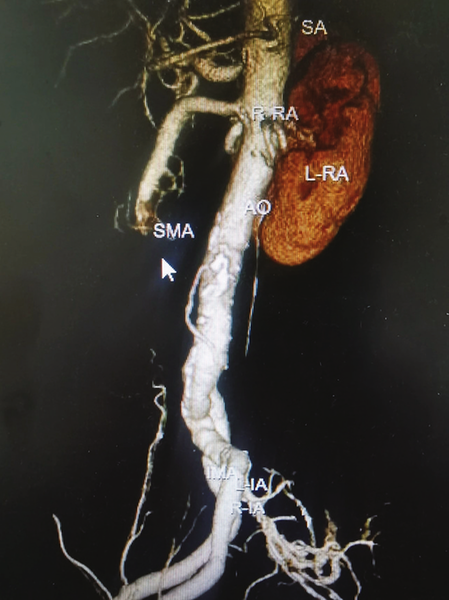

面对肠系膜上动脉栓塞这样的危急重症,陈曦医生深知时间就是生命。确诊后,急诊外科立即启动救治流程,迅速完成术前准备。术中,急诊外科李河圣主任医师在探查患者腹腔情况后决定实施肠系膜上动脉切开取栓手术。李河圣主任医师凭借着多年积累的精湛技术和稳定的心理素质,小心分离肠系膜上动脉周围的组织,精准暴露肠系膜上动脉的起始段,并提前联系介入血管外科及心脏大血管外科医师进行术中会诊。经过多位专家的通力协作,成功使用球囊在肠系膜上动脉中取出栓子,并对切开的肠系膜上动脉进行了完美的缝合修复,手术成功恢复了部分小肠的血运,避免了短肠综合征的发生。

腹部增强CT:图中标识处以远造影剂未显影提示血管栓塞